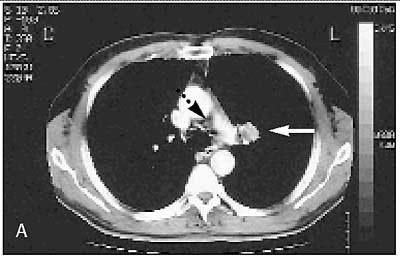

| Scanbeeld van longkanker, gezien vanaf het hoofd richting de voeten (middelste illustratie). De witte pijl geeft de tumor aan. De zwarte gestippelde pijl een nabijgelegen lymfeklier. Aan de lymfeklier is niets opvallends te zien. Een opname met de PET-scan vanuit dezelfde richting levert echter een heel ander resultaat op (onderste illustratie). Bij de witte pijl is de tumor zichtbaar. Links daarvan, bij de zwart gestippelde pijl, dezelfde lymfeklier. Het feit dat deze donker verkleurd is, wijst op de aanwezigheid van uitgezaaide tumorcellen in de lymfeklier.

Scanbeelden J. W. G. van Putten |